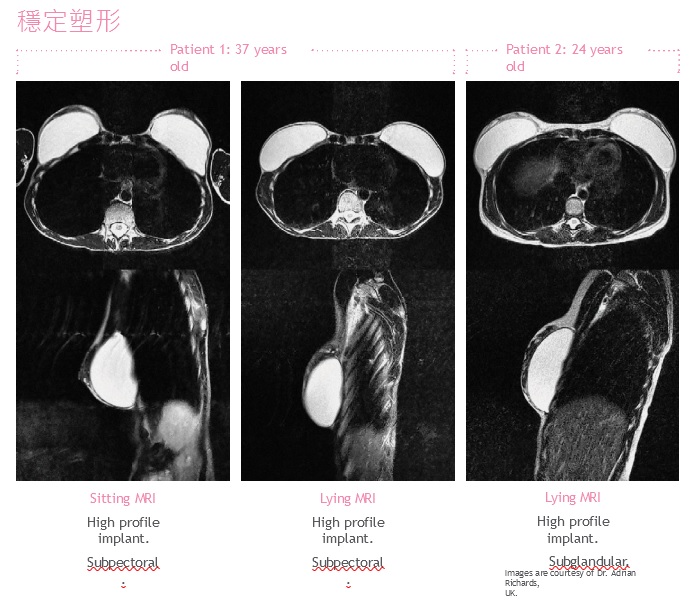

♦凝膠的設計具有塑形穩定性,透過MRI顯示,在站立和仰臥位置能顯示自然乳房組織輪廓。